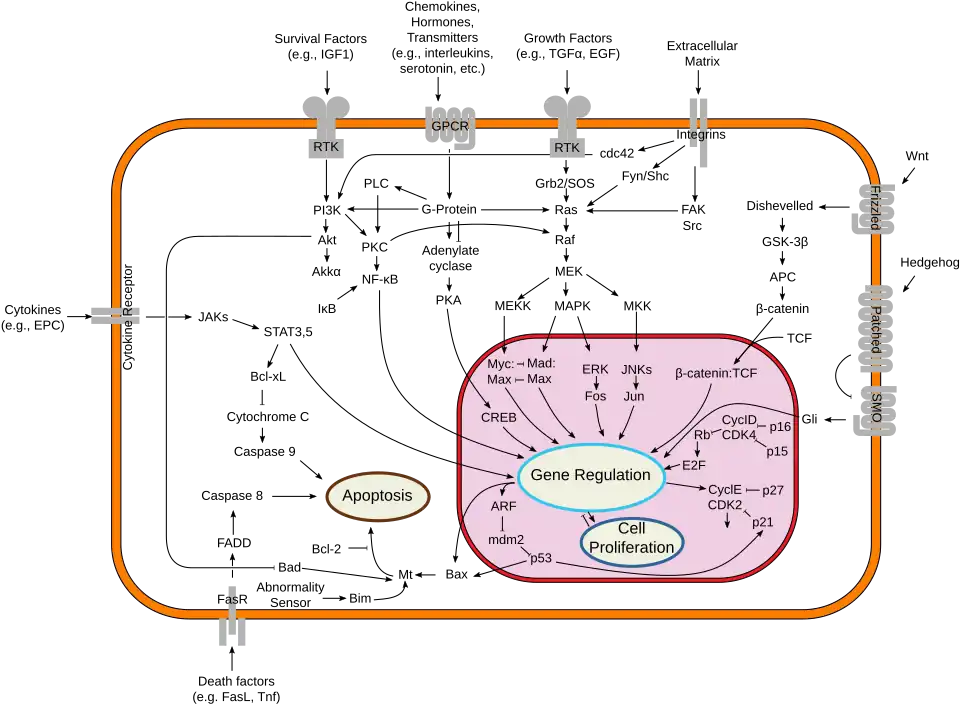

Cytokine receptors are receptors that bind to cytokines.[1] The binding of cytokines to receptors allows the cell that houses the receptor to be able to receive the signals of another cell. These receptors can be found on the surface of cells that allows them to communicate with other cells that transmit their signals [2]This interaction between cells can involve genetic output, cell cycle changes and other signal transduction responses. Cytokine Receptors play a crucial role in Immunological response.

In recent years, the cytokine receptors have come to demand the attention of more investigators than cytokines themselves, partly because of their notable characteristics, and partly because a deficiency of cytokine receptors has now been directly linked to certain debilitating immunodeficiency states. In this regard, and also because the redundancy and pleiotropy of cytokines are a consequence of their homologous receptors, many authorities are now of the opinion that a classification of cytokine receptors would be more clinically and experimentally useful.

Some cytokine receptors have complex structures, with many of them being multi-chain receptors. This is because a cytokine receptor's structure determines its function, and which cytokines will be specific for that receptor. Because of this, a classification of cytokine receptors based on their three-dimensional structure has been attempted. (Such a classification, though seemingly cumbersome, provides several unique perspectives for attractive pharmacotherapeutic targets.)

Cytokines and their receptors have a major part in the process of the human body's defense systems, Haematopoiesis, and the proliferation of immune cells.[5] Because of this, many scientists have recognized the potential utilizations that cytokine receptors can have for pharmaceutical treatments. Although cytokine receptors have been studied and documented for decades, there are still ongoing studies that are discovering new functions that pertain to immunology and pharmaceutical applications.

Among these applications is the involvement in cytokines and cytokine receptors in treating immune-mediated inflammatory diseases. These diseases occur when cytokines and cytokine receptors are dysregulated, leading to damage to the tissues and unregulated inflammation in the body. To combat these types of diseases, scientists have developed multiple cytokine receptor-targeting treatments. These newly developed treatments can combat several inflammatory and immune diseases, including rheumatoid arthritis, asthma and psoriasis.[6]

Because of the nature of cytokine's pleiotropy, this introduces potential obstacles to utilizing cytokines and cytokine receptors in pharmaceutical and clinical applications.[7] This is because the ability for cytokines to be able to interact with multiple cell types makes it difficult to utilize their characteristics in a clinical setting.